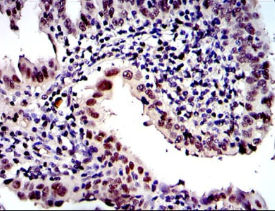

PSMB8 Mouse Monoclonal antibody[1A5H2]

The proteasome is a multicatalytic proteinase complex with a highly ordered ring-shaped 20S core structure. The core structure is composed of 4 rings of 28 non-identical subunits; 2 rings are composed of 7 alpha subunits and 2 rings are composed of 7 beta subunits. Proteasomes are distributed throughout eukaryotic cells at a high concentration and cleave peptides in an ATP/ubiquitin-dependent process in a non-lysosomal pathway. An essential function of a modified proteasome, the immunoproteasome, is the processing of class I MHC peptides. This gene encodes a member of the proteasome B-type family, also known as the T1B family, that is a 20S core beta subunit. This gene is located in the class II region of the MHC (major histocompatibility complex). Expression of this gene is induced by gamma interferon and this gene product replaces catalytic subunit 3 (proteasome beta 5 subunit) in the immunoproteasome. Proteolytic processing is required to generate a mature subunit. Two alternative transcripts encoding two isoforms have been identified; both isoforms are processed to yield the same mature subunit.

Species Reactivity:    Human,Rat

IHC    1/200 - 1/1000